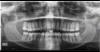

Hammas Опубликовано 9 июня, 2009 Автор Поделиться Опубликовано 9 июня, 2009 PROBUY ESHE RAZ Ссылка на комментарий

Hammas Опубликовано 9 июня, 2009 Автор Поделиться Опубликовано 9 июня, 2009 I ESHE ODIN Ссылка на комментарий